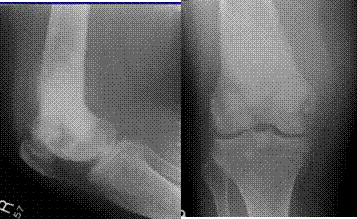

$$$013 Назовите повреждение

A) Сгибательный надмыщелковый перелом плеча

B) Перелом венечного отростка

C) Разгибательный надмыщелковый перелом плеча

D) Перелом локтевого отростка

E) Перелом блока плечевой кости

{Правильный ответ} = D